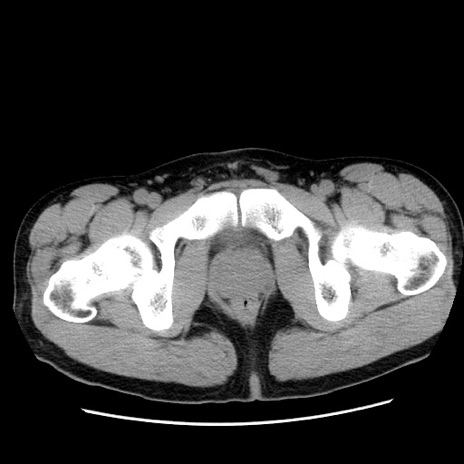

症例36(横断像)

【症例】20歳代 男性

【主訴】心窩部痛

【現病歴】今朝より上腹部痛あり。一旦軽快していたが再度出現したため救急要請。昨日夕に白身の魚を含む刺身を食べた。

【身体所見】BP 136/89mmHg、HR 74/min、BT 37.0℃、腹部:膨満、軟、心窩部に圧痛あり。反跳痛なし、筋性防御なし、腸雑音やや亢進あり。

【データ】WBC 17700、CRP 0.48